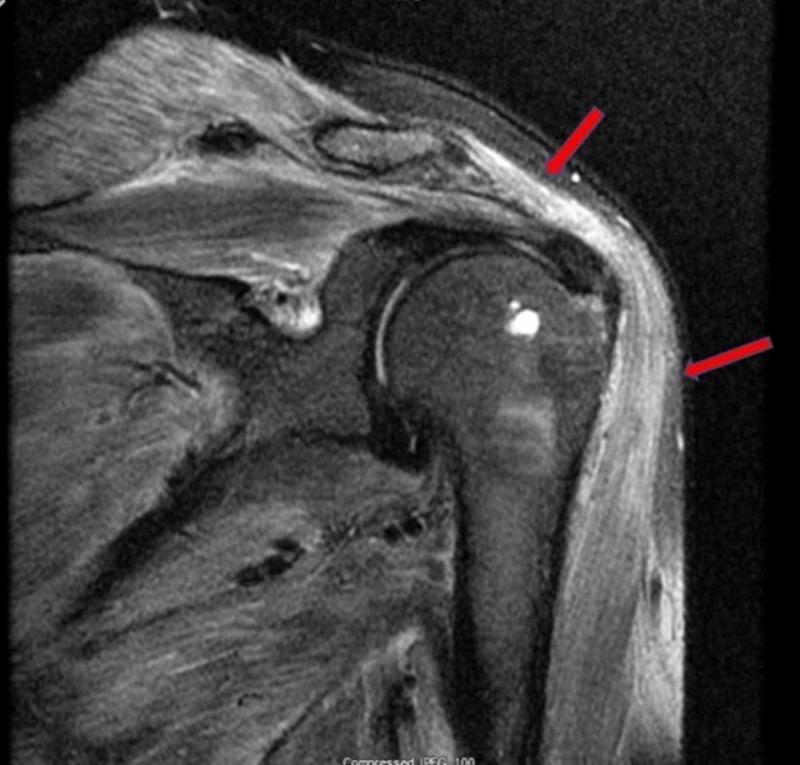

奥美拉唑起始治疗后表现为横纹肌溶解的多发性肌炎

Polymyositis Presenting as Rhabdomyolysis After the Initiation of Omeprazole.

Rhabdomyolysis is a clinical syndrome with a wide range of presentations; it results in muscle necrosis and release of intracellular muscle contents into the circulation. Inflammatory myopathies are a rare cause of rhabdomyolysis. We present a case of a 46-year-old male with a two-week history of progressively worsening diffuse muscle pain after he had been prescribed omeprazole one month prior. A creatine phosphokinase (CPK) elevation was noted, which persisted despite treatment with IV fluids, sodium bicarbonate, and close correction of electrolytes. Further workup, including autoimmune and infectious etiologies, was notable for elevated antinuclear antibodies (ANA), erythrocyte sedimentation rate (ESR), and C-reactive protein (CRP). Furthermore, a muscle biopsy showed evidence of endomysial inflammatory cells, consistent with a diagnosis of polymyositis. Steroids were initiated with significant improvement in symptoms and a decrease in CPK levels. The patient was discharged on a tapering dose of steroids and, on follow-up with the rheumatologist, transitioned to methotrexate with control of symptoms. In patients with rhabdomyolysis who do not respond to first-line therapy, obtaining a detailed medication history and screening with ANA and ESR are encouraged. Given the link between medication and autoimmune disease, clinicians should consider autoimmune myopathy in the differential for cases with persistently elevated creatine kinase. Prompt diagnosis with early initiation of immunosuppressive medication may improve outcomes and avoid complications associated with untreated rhabdomyolysis or polymyositis.

摘要